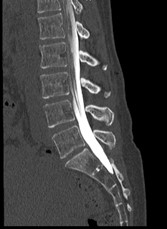

治療について

受診された際には問診、診察を行い、画像検査(レントゲン、MRI、CT)や採血検査を行い、診断を付け、治療方針を説明します。 上記のような保存治療を行っても取れない痛みや、手の使いにくさや歩行困難、排尿排便障害などが出現し症状が進行性の場合は手術加療が必要となります。

手術・検査

なるべく低侵襲で体の負担が少ない手術を行います。低侵襲な脊椎手術には、手術による傷が小さい、筋肉の損傷が少ない、出血量が少ない、時間が短い、術後の痛みが少ない、早期リハビリテーションが可能、早期退院が可能(10日程度)、早期社会復帰が可能、など多くの利点が挙げられます。

検査

当院では、術前の診断精度を高める目的で、神経根ブロック(左)やCTミエログラフィー(右)検査を行っています。検査後は、経過を確認する目的で1泊入院となりますが、翌日には退院が可能です。